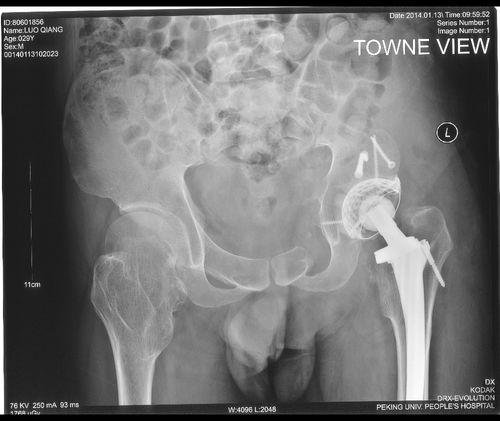

股骨头手术通常分为两种:切开复位内固定术和人工股骨头置换术。以下,我们就以切开复位内固定术为例,看看手术的全过程。

- 固定骨折:使用钢板、螺丝等材料,将骨折部位固定。